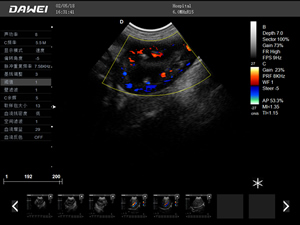

·支持彩色多普勒、頻譜多普勒、能量多普勒、連續多普勒等成像技術

彩色多普勒動物超聲診斷儀